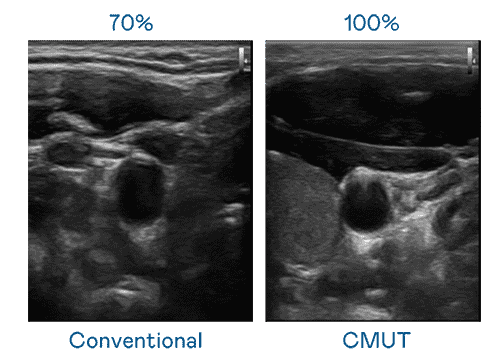

CMUT 技术是一种用电容式微机电元件来产生超音波讯号的技术。。。。与传统 PZT 压电式技术相比,,,,CMUT 频宽增加 30%,,,,更宽频的超音波讯号让影像解析度大幅提升,,,,是实现高影像品质医疗超音波扫描、、促进精准医疗发展的关键技术。。。

大频宽带来超清晰影像

超音波影像的解析度高低,,首先取决于探头能发出的讯号频宽。。。z6尊龙 CMUT 可提供高清晰的超音波讯号,,,提供高频宽、、高灵敏度、、、影像纹理细节更高的超音波影像,,,协助医护人员缩短影像判读时间及利用精准的医疗影像进行诊断。。。。